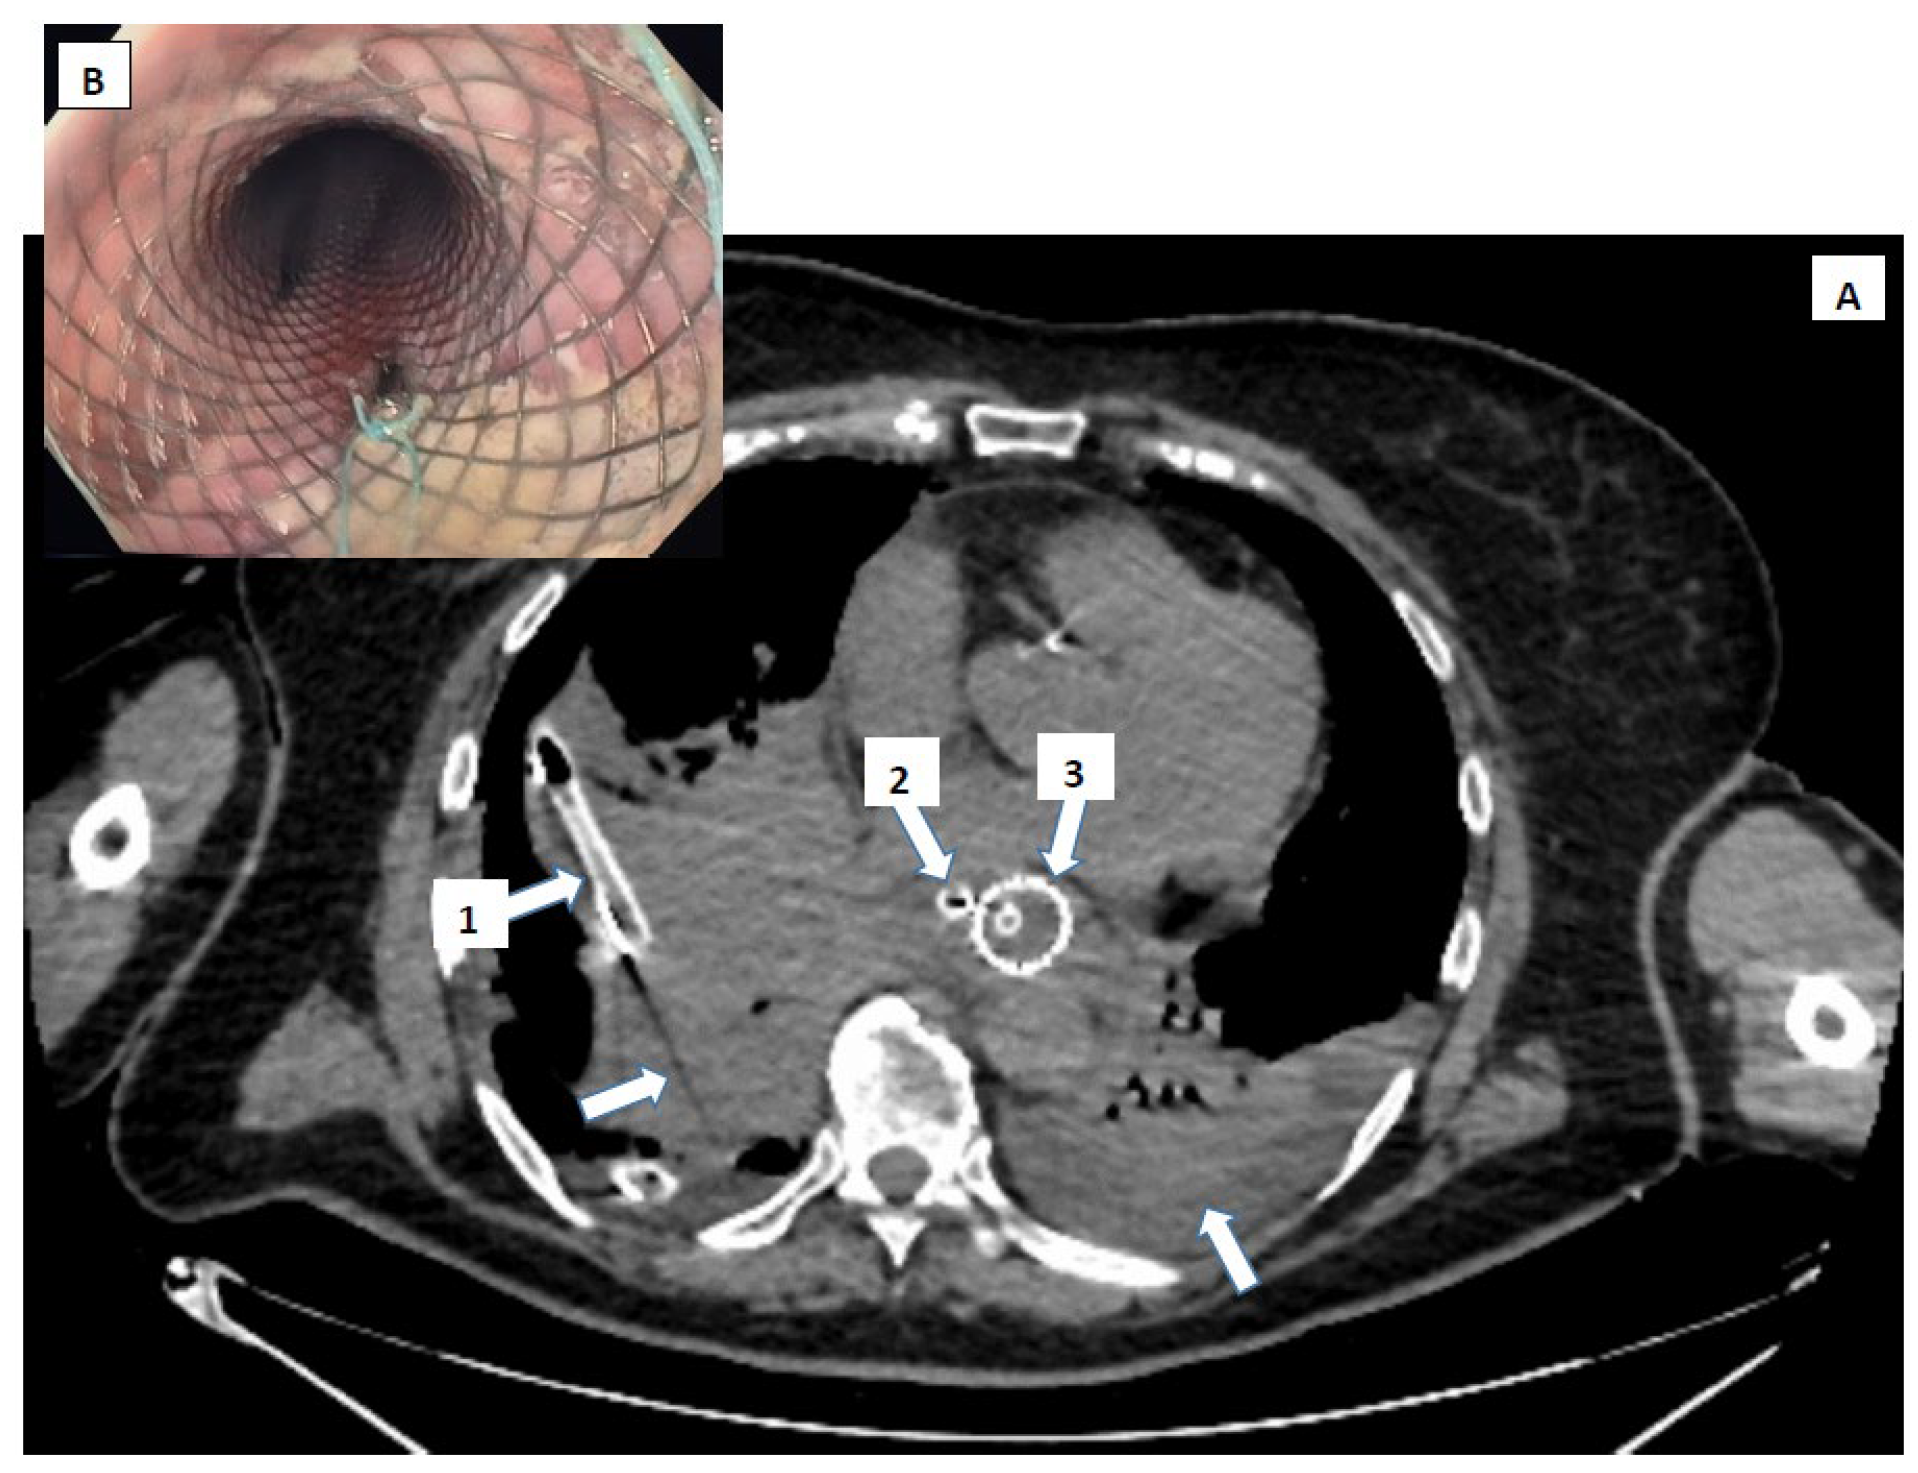

- Pneumomediastinum

- Pneumothorax (especially left-sided)

- Pleural effusion (especially left-sided)

- Localized periaortic gas

- Mediastinal fluid collections

- Thickened esophageal wall

- Gas within thoracic soft tissues, neck, or around major vessels

- Gas in the epidural space

- Pneumoperitoneum

- Gas in the retroperitoneal space

- Oral contrast extravasation from the esophageal lumen [10].